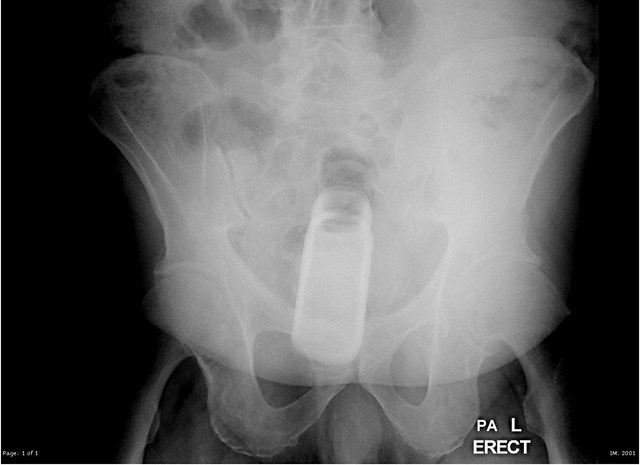

Житель города Волгодонск в Ростовской области, возможно пострадавший от чрезмерного увлечения самоудовлетворением с использованием инородных предметов, угодил в больницу. Дезодорант, который заменял ему фалоимитатор, попросту застрял в заднем проходе. Извлечь вытянутый овальный предмет без помощи медиков ему не удалось. Краснея от стыда, мужчина вынужден был обратиться за помощью в хирургическое отделение БСМП Волгодонска. Специалисты провели двухчасовую операцию по извлечению дезодоранта из заднего прохода. В результате проведенной операции дезодорант был удален. Причины такого поступка мужчина не объяснил. Пациент уже выписан из больницы. Как стало известно «Блокноту Волгодонска», инцидент произошел в августе этого года.

Специалисты провели двухчасовую операцию по извлечению дезодоранта из заднего прохода. В результате проведенной операции дезодорант был удален. Причины такого поступка мужчина не объяснил. Пациент уже выписан из больницы. Как стало известно «Блокноту Волгодонска», инцидент произошел в августе этого года.